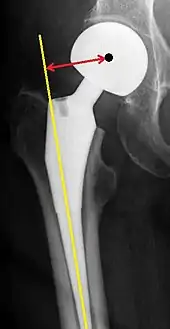

Center of rotation: The horizontal center of rotation is calculated as the distance between the acetabular teardrop and the center of the head (or caput) of the prosthesis and/or the native femoral head on the contralateral side.[80] The vertical center of rotation instead uses the transischial line for reference.[80] The parameter should be equal on both sides.[80]